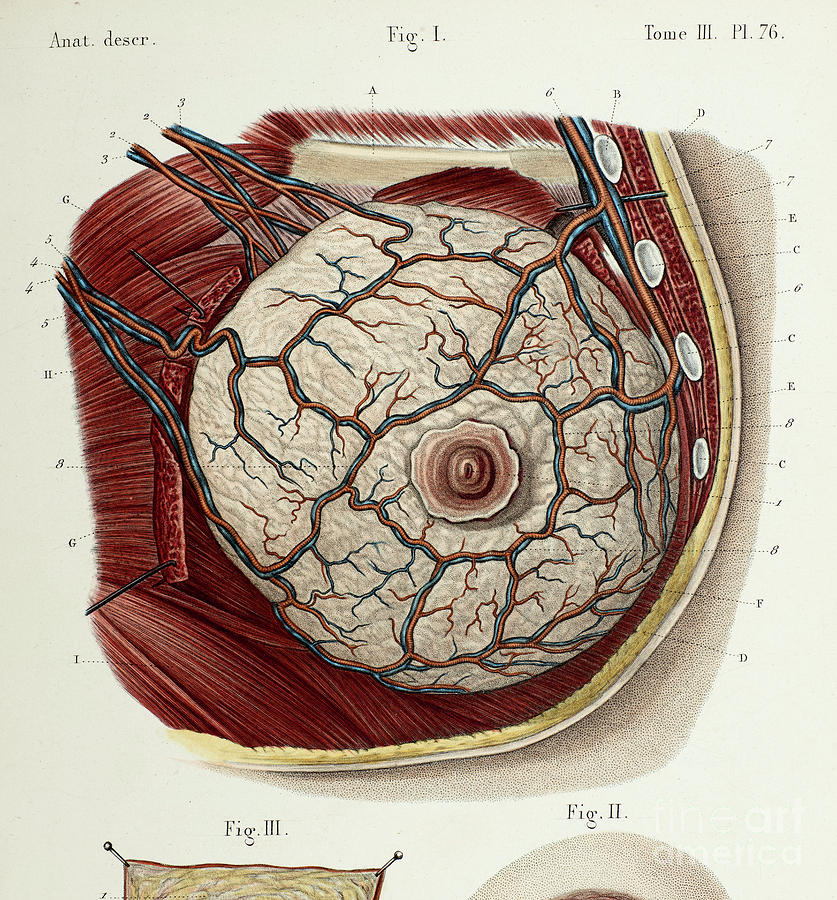

Breast anatomy artwork Stock Image C014/8562 Science Photo Library

Photograph Breast Anatomy Illustration Science Source Images

Female Breast Anatomy #2 Photograph by Science Photo Library Pixels Merch